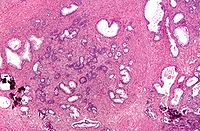

Dans l'HBP, l'architecture de la prostate est globalement préservée avec un aspect nodulaire, mais il existe une hyperplasie des différents constituants.

Les glandes prostatiques sont en nombre augmenté, bordées par une double assise épithéliale. Elles sont souvent le siège de dystrophie (kystisation) ou d'atrophie, et de phénomènes inflammatoires. Les cellules musculaires lisses sont également en nombre augmenté, de même que les fibroblastes de l'interstitium.

L'hyperplasie respective des différents constituants (épithélial, musculaire lisse et fibroblastique) est d'intensité variable suivant les territoires examinés.

![]() |

![]() | |

Histologie d'une prostate normale |

Histologie d'une hypertrophie bénigne de la prostate |